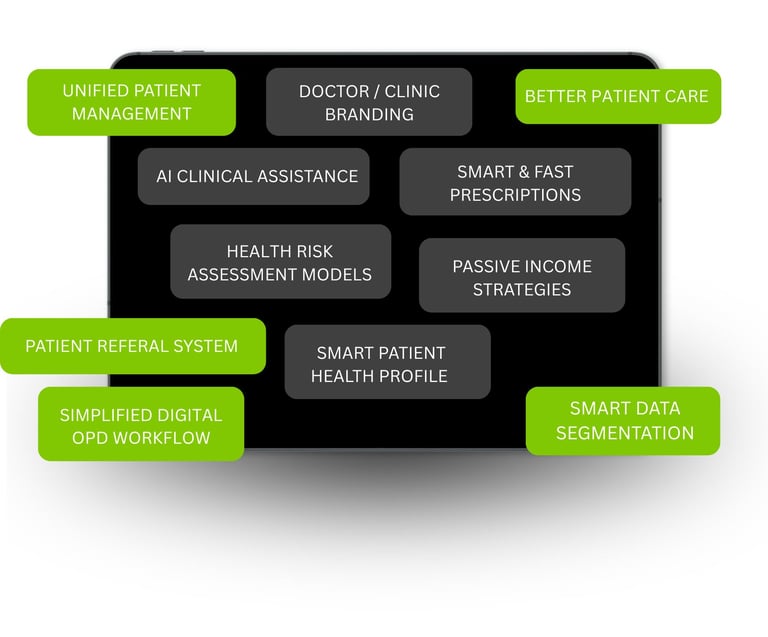

PHIA.CARE helps doctors run smarter Clinics / Polyclinics with AI-assisted prescriptions, instant risk reports, and fully digital patient management—so you focus on treatment, not paperwork.

We empower Doctors, clinics and hospitals with our technology-enabled platform, enabling efficient and structured patient management through single account and health risk evaluations at the OPD level.

THE SOLUTION

PHIA.CARE is your digital clinic assistant.

It simplifies everything—from patient entry to follow-up

Saves time.

Better follow-up.

Profesional websites and branding

Better patient experience through personal health profiles for them.

Easy OPD workflows in few taps.

Increased revenue.

AI assisted health summaries & prescription writing